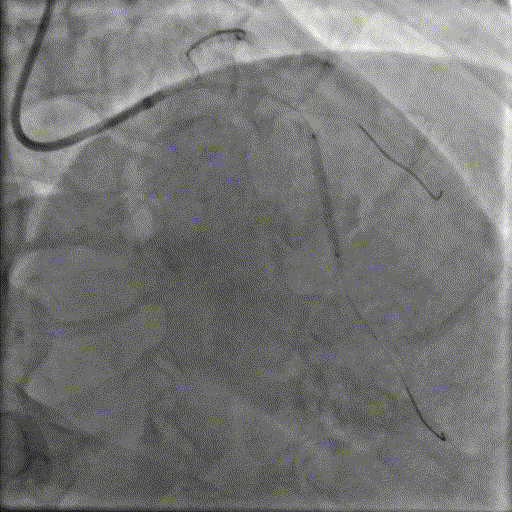

当导丝通过病变后其他器械无法通过病变,此时选择不同尺寸的小球囊逐级预扩张病变,复查造影狭窄减轻不明显。为了解血管真实情况,遂启用IVUS检查。

术前腔内影像学IVUS指导

IVUS提示血管可见钙化明显,为360°环形钙化。遂考虑启动IVL治疗。

冲击波球囊治疗

2.5*12mm@4atm 冠脉血管内冲击波导管反复进行4个周期治疗,复查造影提示狭窄减轻。

支架植入并后扩

于OM2-LCX远端植入一枚药物洗脱支架,经非顺应性球囊后扩张支架,复查造影提示支架贴壁良好,未见夹层、血肿。